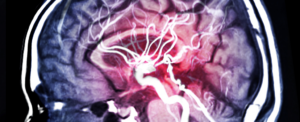

Нові назальні краплі можуть сприяти відновленню мозку після інсульту

Інсульт є серйозним захворюванням, яке може призвести до пошкодження мозку і втрати функцій. За допомогою цих нових назальних крапель, які містять спеціальні речовини, вчені змогли активувати регенерацію тканин мозку, що дозволяє йому відновитися швидше та ефективніше.